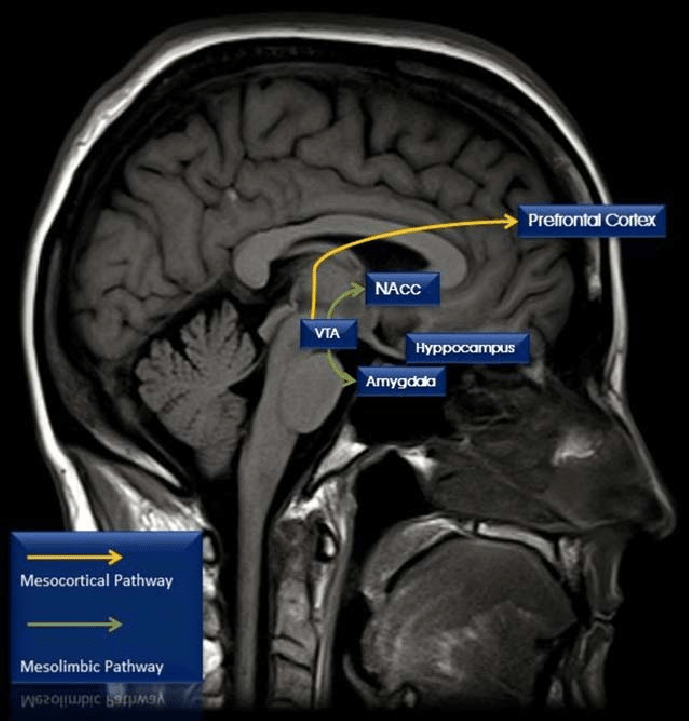

Cocaine is a psychostimulant, meaning it temporarily boosts brain activity. When someone first takes cocaine, they often briefly feel happier, more confident, alert, and physically energised. Cocaine affects several neurotransmitters in the brain, but its main impact is on a group called the monoamines, especially dopamine, which is heavily involved in feelings of reward and pleasure. The brain circuit most affected by this is called the mesocorticolimbic system, seen in Figure 1, which normally activates in response to everyday pleasurable experiences. This pathway starts in the ventral tegmental area (VTA), which is a part of the midbrain and contains neurons responsible for the release of dopamine in order to interact with areas like the nucleus accumbens and the medial prefrontal cortex, both of which are important for motivation, decision-making, and emotion. Cocaine and similar drugs disrupt this system by stopping the reabsorption of dopamine through blocking dopamine transporters. This causes a buildup of dopamine, which strongly boosts the brain's reward signals, and causes the previously mentioned effects of alertness and happiness.